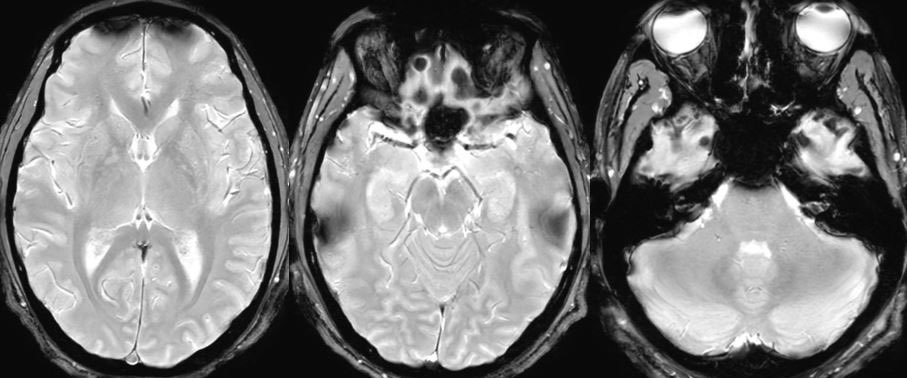

Imaging Findings → White Matter Hyperintensities T2-weighted FLAIR MRI showed bilateral periventricular and deep white matter hyperintensities, consistent with small vessel ischaemic changes. These lesions are often linked to vascular depression and late-onset psychosis. Psych Scene Tip: In late-onset depression or new-onset psychosis, always consider cerebrovascular contributions.

A 59-year-old woman with no prior psychiatric history presented with severe depressive symptoms, nihilistic delusions, and poor insight. She required inpatient admission due to suicidality and functional decline. Let’s examine this case and its imaging to highlight the diagnostic and management considerations. 🧵👇